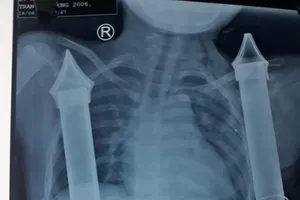

Cấp cứu thành công nam thanh niên bị ống sắt lan can cầu đâm xuyên vùng bẹn Y tế - Sức khỏe 10/09/2021 19:15